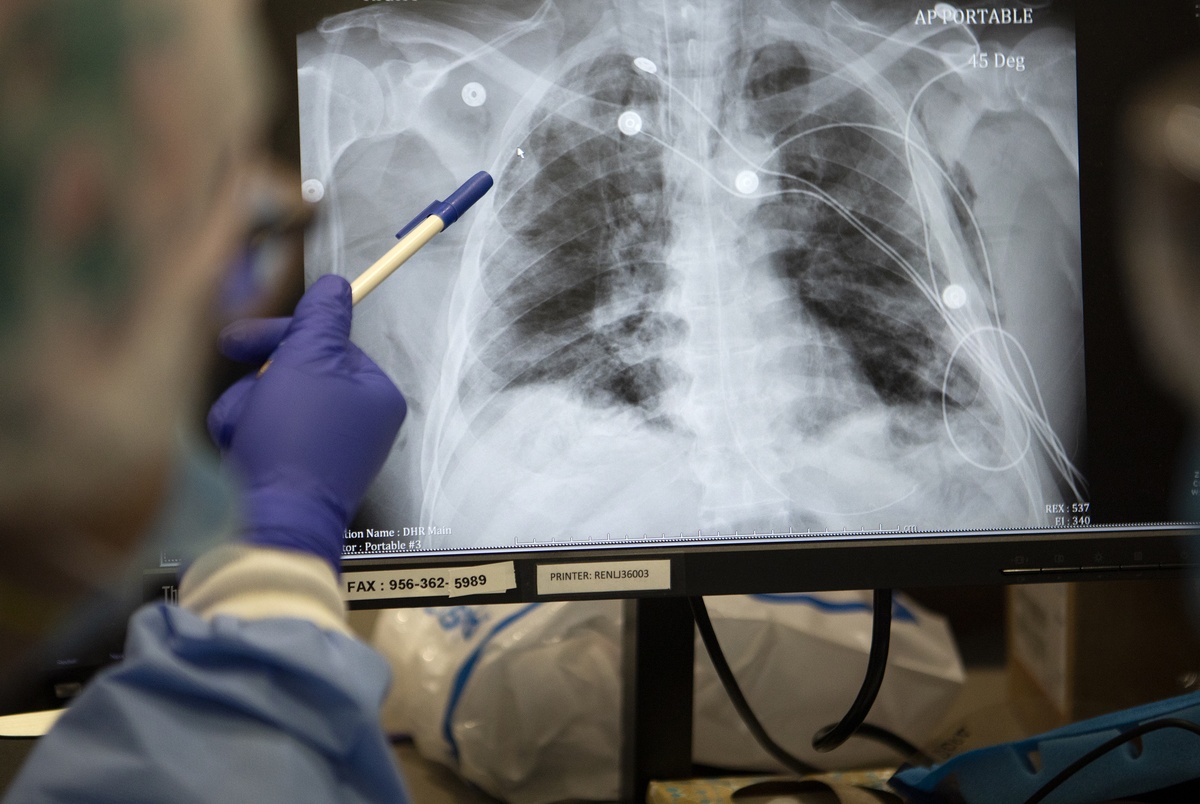

Radiologists Sharing Ct Scans X Rays In Global Effort To Prevent Covid 19 Deaths Abc News

www.abc.net.au